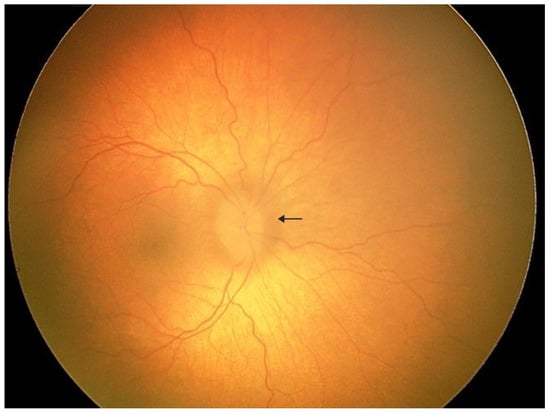

Geleophysic dysplasia (GD) is a rare genetic skeletal disorder belonging to the acromelic group, characterized by short stature, distinctive facial features, thickened skin, and progressive cardiac involvement. We report a case of a 3-year-old boy with GD caused by a heterozygous c.5198G>A variant in the FBN1 gene, presenting with ocular abnormalities. The patient demonstrated coarse facial features, short hands and feet, and a history of mitral valve stenosis requiring mechanical valve replacement. He was referred to the ophthalmology department for evaluation of left eye strabismus and elevated intraocular pressure. Fundus examination revealed a pink optic disc with blurred margins, slightly elevated above the retinal plane, absent foveal reflex, and tortuous vessels, consistent with optic disc drusen on ocular ultrasonography. Photopic negative response (PhNR) testing showed markedly reduced amplitudes in both eyes, indicating retinal ganglion cell dysfunction. Pattern VEP revealed normal P100 latencies in both eyes, with a 30% reduction in amplitude in the left eye, likely related to poorer fixation. This case highlights optic disc drusen and retinal ganglion cell dysfunction as potential ocular manifestations of geleophysic dysplasia, emphasizing the need for comprehensive ophthalmologic evaluation in affected patients.